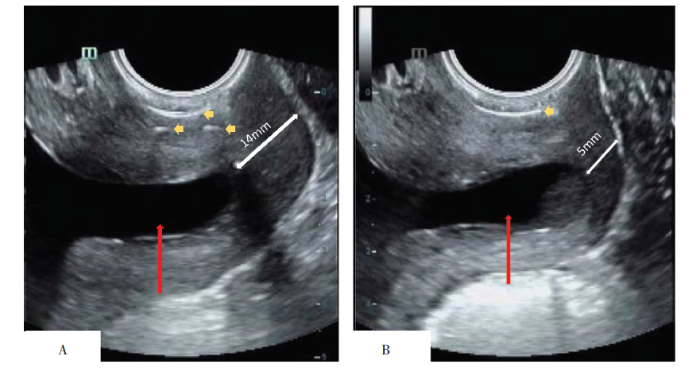

图3

2020年9月22日双侧宫颈管变化超声对比图

注:A 行单线宫颈环扎术的左侧宫颈管,B 行双线宫颈环扎的右侧宫颈管;红色箭头所示为羊膜囊突入宫颈管,白色箭头所示为剩余宫颈管长度,黄色箭头所示为环扎线强回声。

1 病例报告

2020年9月22日(21+2周) | 14/5 | U/U | 12/12 | 27/32 |